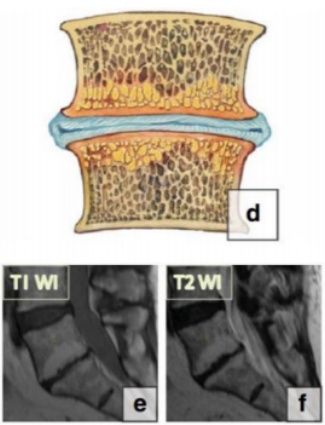

2009 年,Fayad 等在经典分型基础上,提出混合型的分型:

Modic I-2 型:混合性水肿和脂肪改变,以水肿为主;

Modic II-1 型:混合性水肿和脂肪改变以脂肪变性为主。